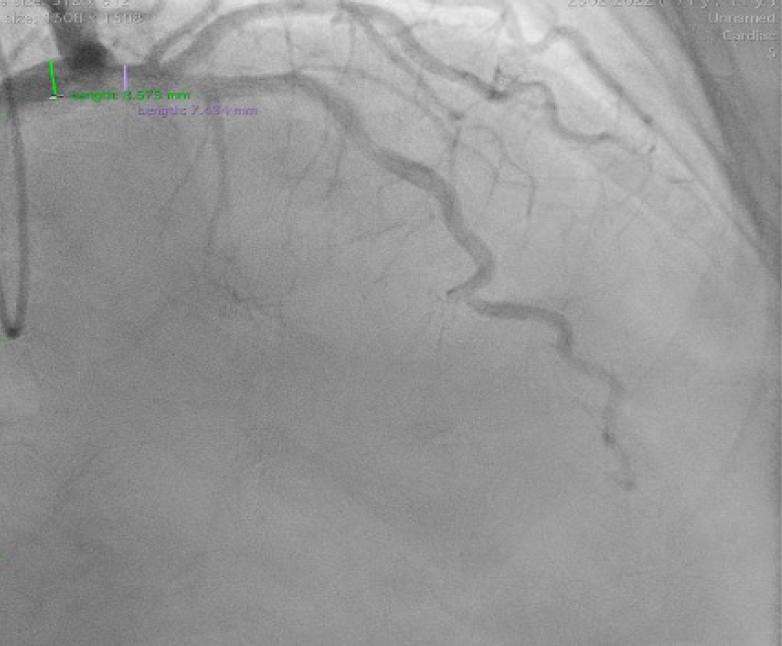

Left main coronary artery (LMCA) was also ectatic (maximum diameter of 10.3 mm in the mid-distal segment), as well as the left anterior descending (LAD) and left circumflex (LCx) arteries (with maximum diameters of 7.4 mm and 8.5 mm, respectively) (Figs. 3–4). Slow coronary flow was present in all vessels.

Cranial right anterior oblique projection of the left coronary artery. Optimal projection of the left anterior descending artery (LAD) showing an ectatic vessel, with a maximum diameter of 7.4 mm in the proximal segment.